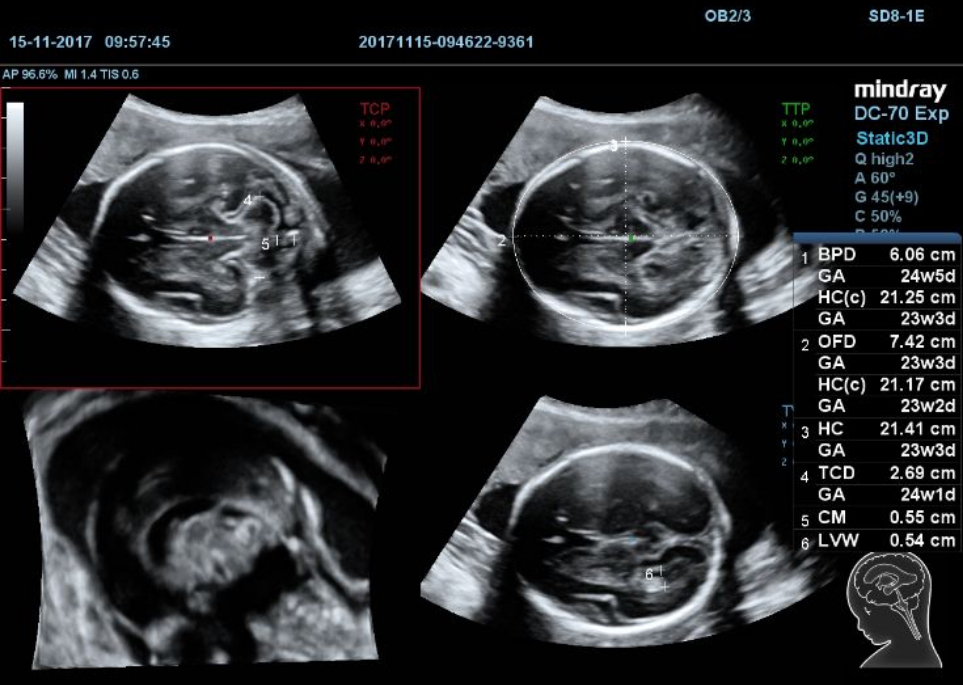

Smart Planes CNS

Accuracy with smart acquisition

Previously, it could be a challenge to acquire the MSP from fetal central nerve system, especially for a fresh hand, who might find the difficulty in recognizing some views of the anatomy from a totally unfamiliar display very daunting initially. Even for experts it’s never an easy job. According to a report, it usually takes a skilled sonographer between 65 and 186 sec to manually acquire the MSP (Yang J, Yuan J & Qu X, 2012).

To boost the efficiency, Mindray has developed a remarkably easier way to get it done.

Just acquire the 3D dataset of the fetal head and hit a button, then the standard CNS scanning planes (MSP, TCP, TTP and TVP) are obtained automatically. If you press Auto Measure, a range of anatomical measurements (BPD, HC, OFD, TCD, CM and LVW) will be displayed immediately with outstanding accuracy, within a second. The entire process takes less than a minute yet the images are of even higher quality than those acquired in the conventional method.